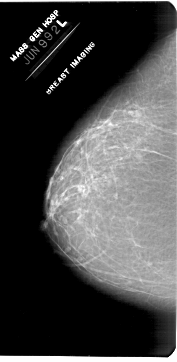

A_1953_1.LEFT_CC

LEFT_CC LINES 6871 PIXELS_PER_LINE 3361 BITS_PER_PIXEL 12 RESOLUTION 43.5 NON_OVERLAY